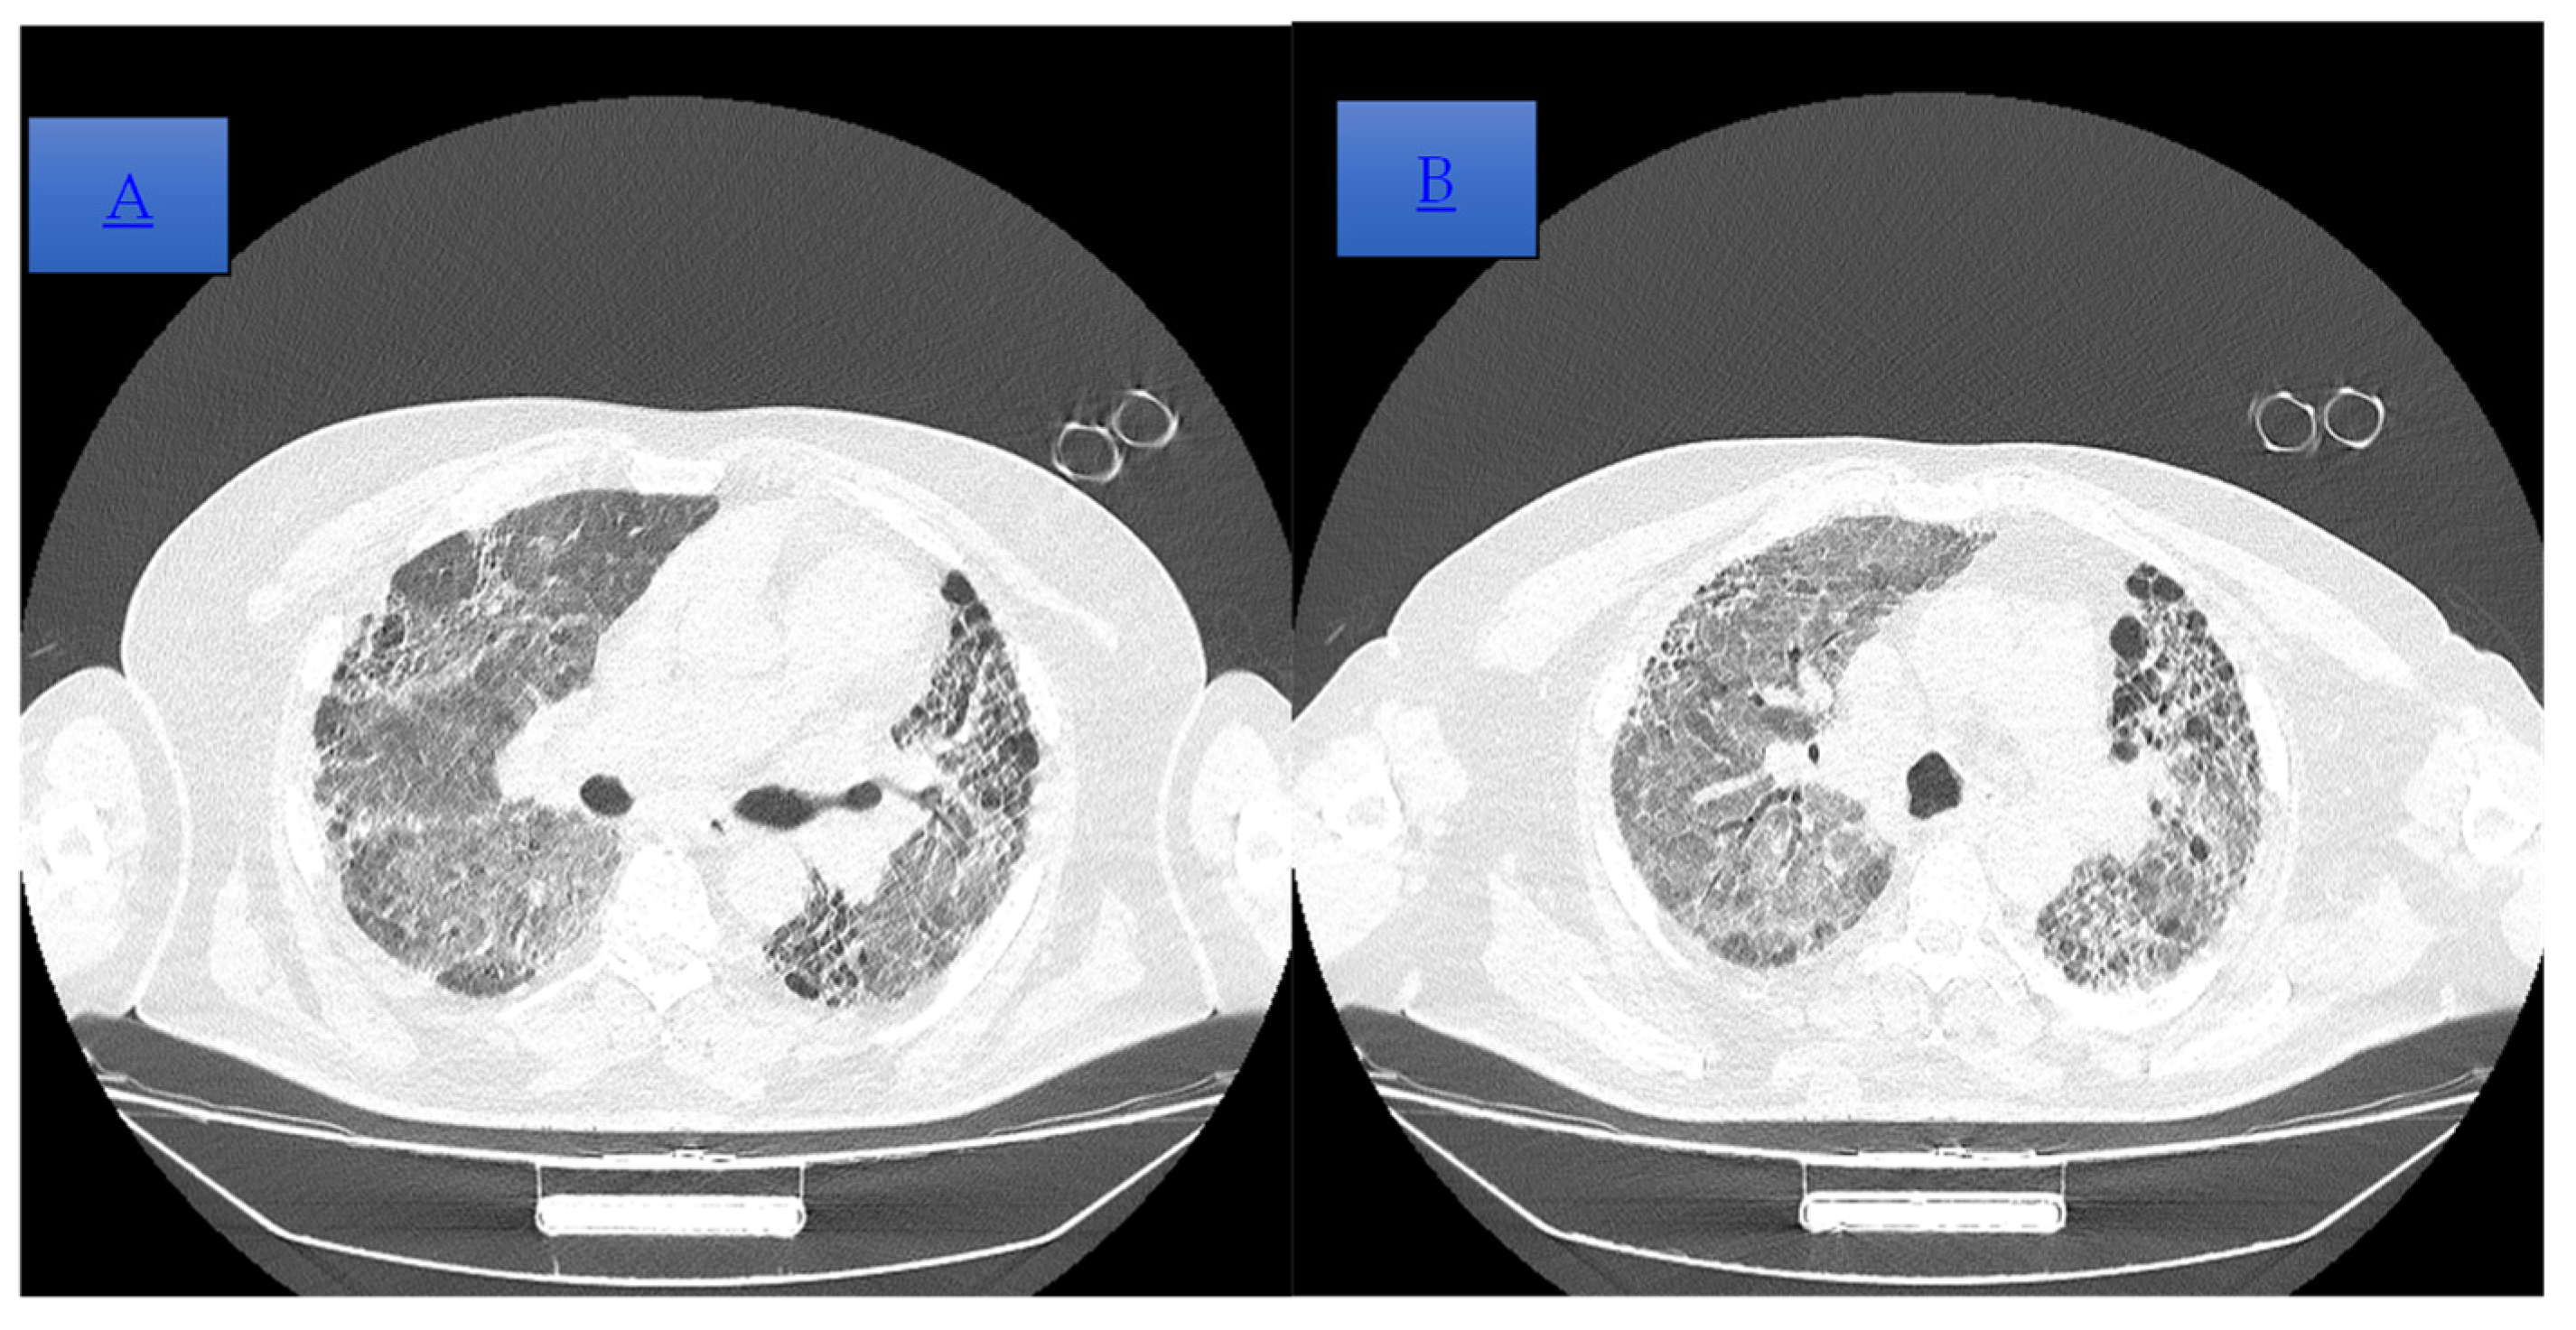

Figure 3. (A,B) Cranio-caudal dispersed reticulonodular opacities, which associate the traction and cylindrical bronchiectasis, on the right lung and cystic on the left basal lung, with an imaging aspect that illustrates end-stage pulmonary fibrosis (UIP pattern). The association of extensive ground-glass opacities is associated with the extensive inflammatory process (NSIP pattern). Global cardiomegaly with a dilated pulmonary trunk shown.